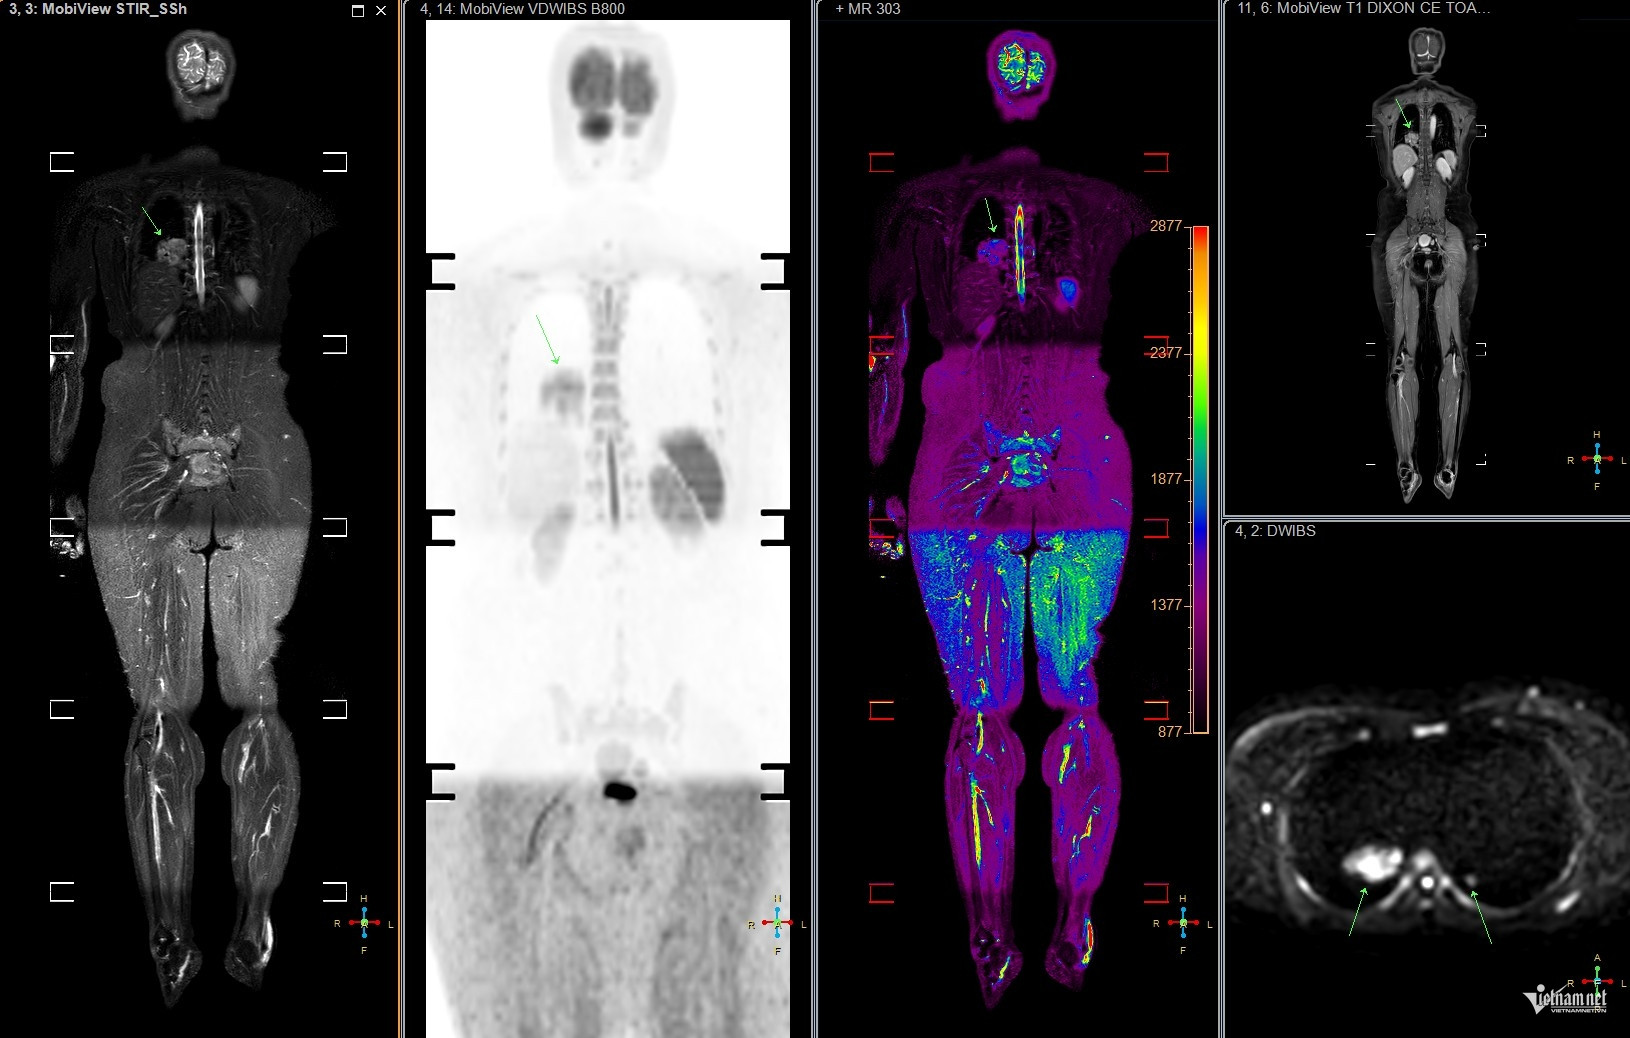

Hình ảnh MRI toàn thân của bệnh nhân ung thư phổi. Ảnh: Minh Đức.

Tại bệnh viện, sau khi thực hiện các xét nghiệm và chụp chiếu, bác sĩ phát hiện chị T. có khối u ở phổi và các nốt mờ ở xương do di căn. Kết quả này khiến vợ chồng chị và bạn bè thân thiết bàng hoàng. Nhìn vào tấm phim MRI, từng nốt mờ ở phổi và xương được bác sĩ chỉ rõ, những lời giải thích như khắc sâu vào tâm trí chị.

Về việc tầm soát sớm ung thư phổi, giáo sư Khoa cho biết những người có yếu tố nguy cơ như hút thuốc lá chủ động, thụ động có thể thực hiện qua chụp CT liều thấp, giúp phát hiện tổn thương nhỏ. Các kỹ thuật hiện đại như PET, PET/CT, PET/MRI, kết hợp với sinh học phân tử, hỗ trợ xác định đột biến gene, từ đó chọn phương pháp điều trị trúng đích.